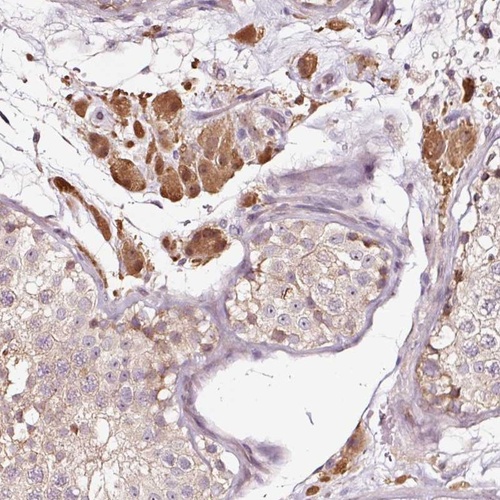

Immunohistochemical staining of human testis shows strong cytoplasmic and nuclear positivity in Leydig cells.